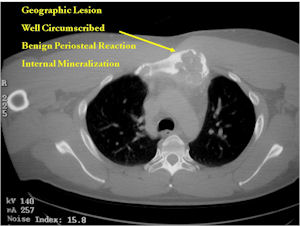

- Geographic, circumscribed lesion usually around 5cm in size.

- There may be expansion of bone, cortical thinning and cortical breakthrough. A soft tissue mass may accompany this lesion but the soft tissue component is usually contained by the periosteum.

- The periosteum remains intact around the soft tissue component. Might need a CT scan to detect the subtle calcification (Egg Shell Rim of Calcification) associated with an intact periosteal reaction

- The lesion may be entirely radiolucent but usually shows some degree of mineralization. Mineralization may appear stippled like cartilage but do not see chondroid pathologically. Mineralization is sometimes better detected on a CT scan rather than an x-ray.

- More useful for detecting mineralization and evaluating extent of bone destruction than plain X-ray

- There is often extensive edema around the tumor in the surrounding bone and soft tissues that can lead to a misdiagnosis of a malignant tumor.